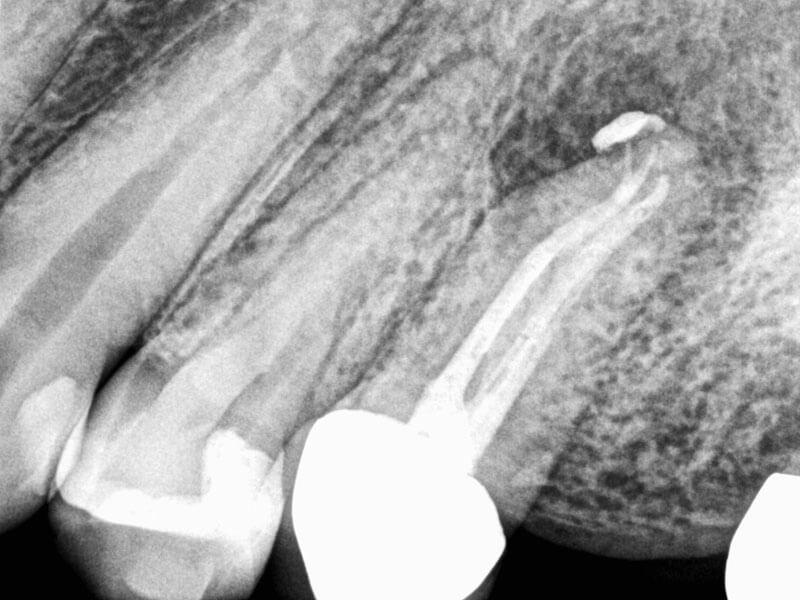

Patient was referred for apical surgery after previous endodontic treatment was unsuccessful. After retreatment with the GentleWave® Procedure with ProControl™, adjusting NaOCl to 5%, the patient's symptoms completely resolved within 48 hours.